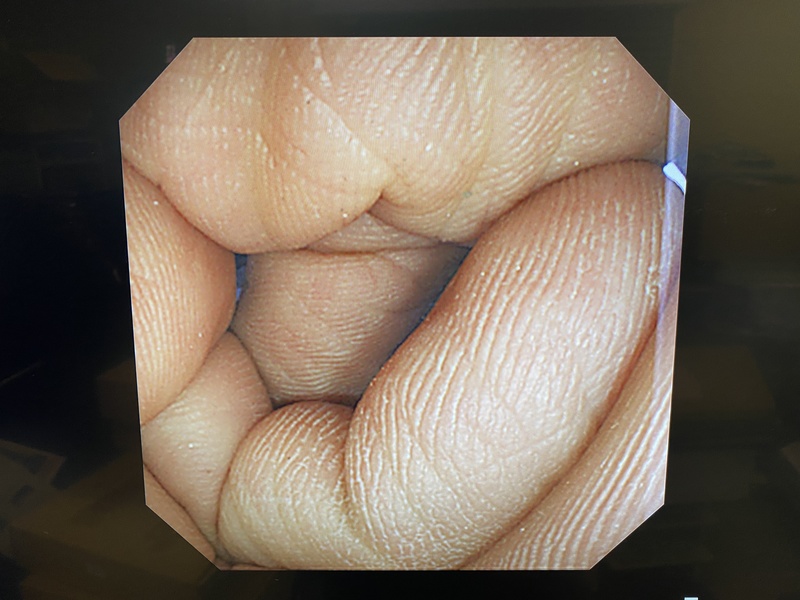

- detail Video Colonoscope / 17198 / CF-240AI